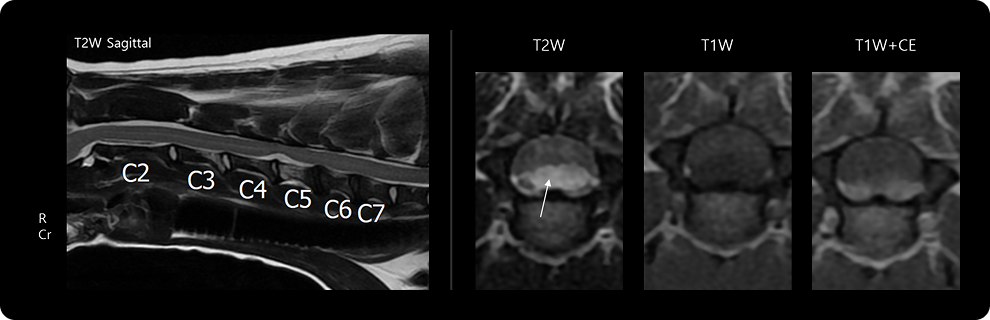

디스크의 형태적인 분류는 MRI와 같은 영상 정밀검사를 통해 평가 및 구분되어집니다. 이러한 형태적인 차이들에 대한 정보는 내과적인 치료, 수술적인 치료 등의 치료계획 설정에 있어 중요한 참고 자료로 활용됩니다.

경추

경추 부위에 발생한 디스크 질환은 목의 통증, 사지 마비 증상 및 경직 등의 증상을 보일수 있으며, 병변이 제한 적인 경우 한쪽 앞다리 혹은 편측 압-뒷다리의 마비증상을 보일수 있습니다. 해당 위치의 병변이 심증도일 경우 마비 증상 외에도 호흡곤란, 부정맥 등 경추 부위를 통해 조절되는 흉강의 이상 소견을 유발할 수 있어 생명에 위협될 수 있습니다.